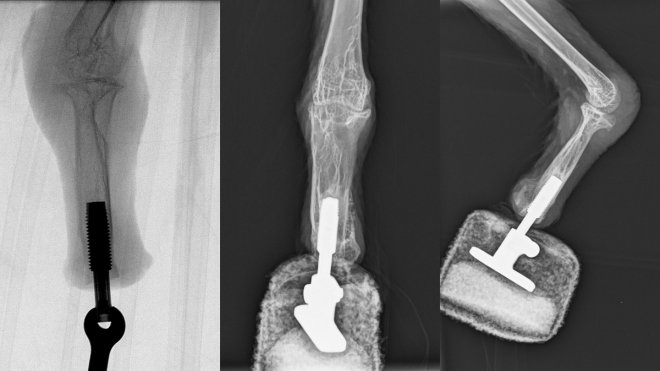

Рентген-снимок протеза лапы

Поэтому было принято решение провести эксперимент по остеоинтеграции, когда протез монтируется непосредственно на остатке кости и впоследствии врастает в нее. В итоге ученые пошли еще дальше – профессор Асманн уже установил три биомеханических протеза с управлением мыслительными импульсами людям, и решил попробовать проделать то же самое с коршуном. Все получилось отлично, Миа начала ходить через три недели после операции, а к шестой неделе уже научилась полностью переносить вес тела на протез.